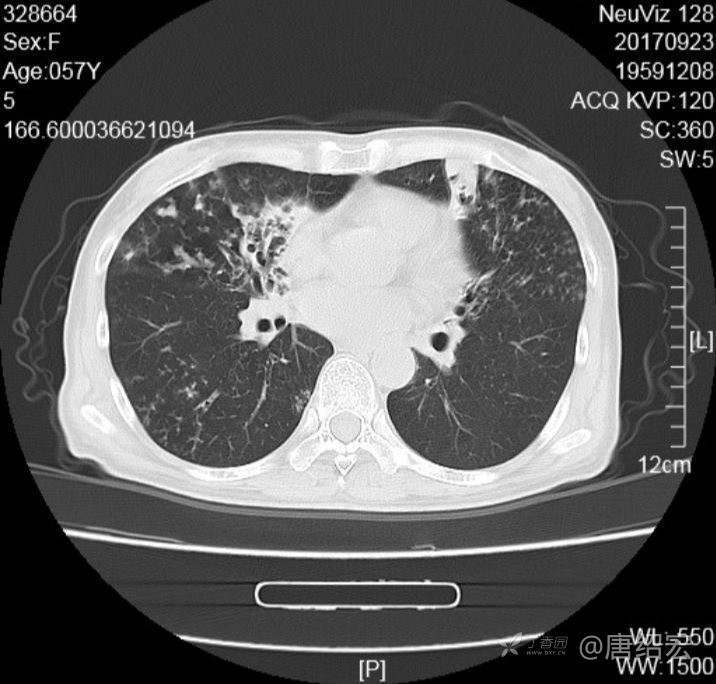

中年女性满肺树芽征还有支气管扩张,考虑什么疾病?

女,57岁,

主诉:发热、咳嗽、咯黄痰,胸闷3天入院。